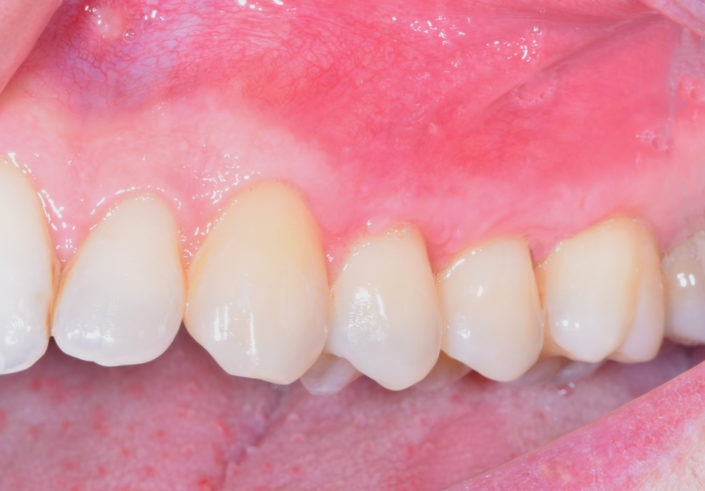

La patiente a été adressée au cabinet par son dentiste traitant pour une solution de remplacement de son bridge maxillaire en fin de vie. Une solution implantaire lui a été proposée pour la réhabilitation de sa mâchoire soit les extractions des dents, mise en place des implants avec aménagement osseux, le tout lors de la même intervention sous sédation vigile. Un Bridge fixe implantaire provisoire et esthétique a été placé 48 heures après l’intervention. Cette prothèse restera en bouche au moins 6 mois pour valider les implants, l’esthétique et la fonction avant de passer aux empreintes pour la prothèse finale (bridge céramique) qui sera totalement adaptée et personnalisée à la demande de la patiente.